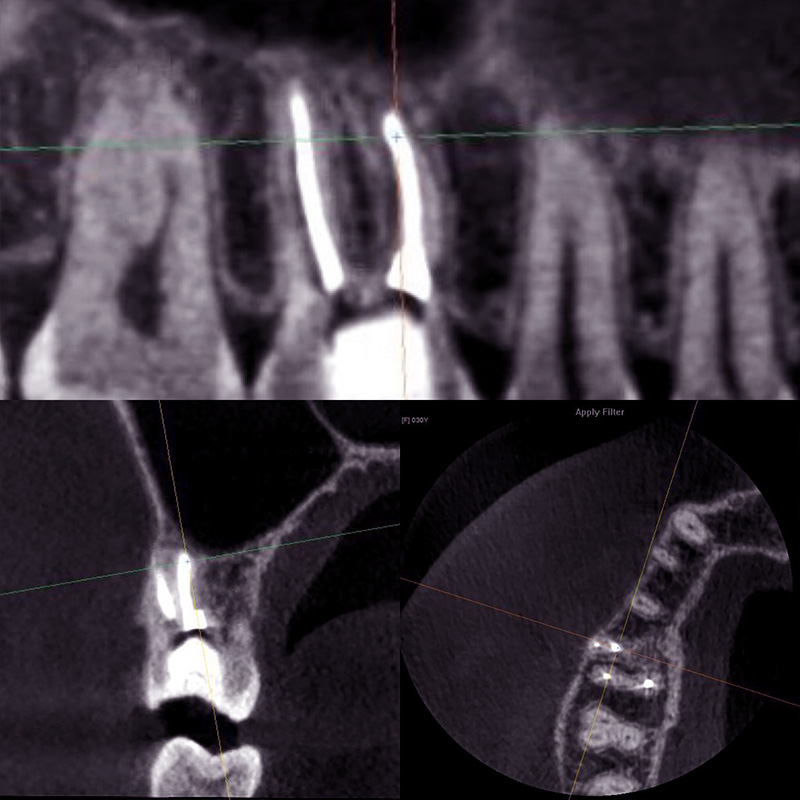

В результате обострения хронического периодонтита и появления ноющих болей проведено пломбирование канала зубаСмотреть работуСрок лечения:2 часаСумма лечения:9 590 руб.